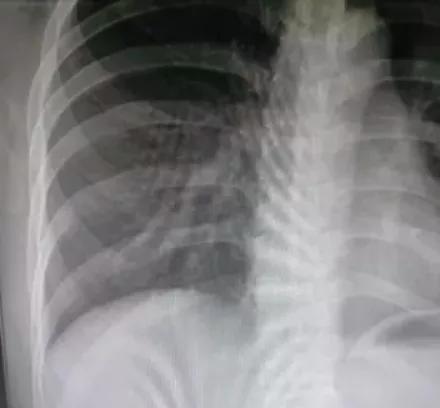

正常呼吸拍摄(同比例局部放大)

在观察肺部和腹部微小病变时,若不屏住呼吸,可能产生呼吸伪影,显示不清,影响图像质量,导致诊断不明确,甚至漏诊。